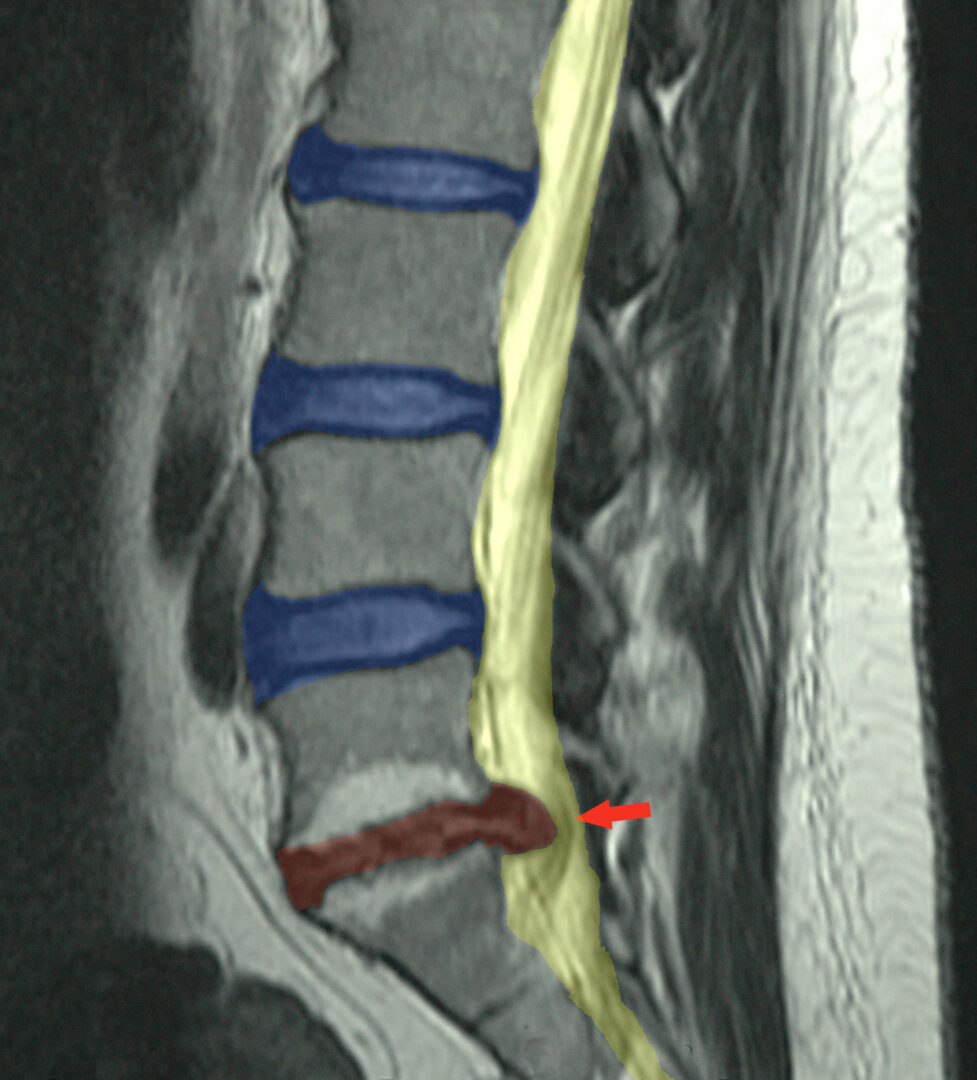

Spinal Decompression, is a non-surgical treatment that utilizes a specialized table to relieve pain by creating a scenario in which bulging or herniated disc tissue is able to move back into place and heal, alleviating the pain this condition causes.

Spinal Decompression Therapy is for patients who are suffering from back pain and/or sciatica and have already been diagnosed with a herniated disc in the lumbar spine. They have either not tried or have not found relief with traditional Chiropractic, Physical Therapy, and/or medical care and wish to avoid surgery at all costs!

Sciatica, pinched nerves, bulging discs, protruding discs, herniated discs, slipped discs, foraminal stenosis, facet syndrome and more.